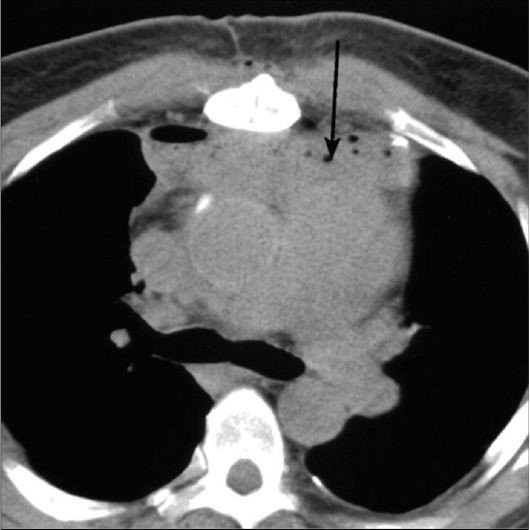

• Klinik, laborator və tomoqrafik üsullarla törəmənin təbiəti məlum olmursa rezektabelliyə görə qərar verilir (Şəkil 20). Rezektabel törəmələrdə kütlə əməliyyatla (torakoskopik və ya açıq) çıxarılır və histoloji müayinə edilir (həm diaqnostika, həm də müalicə məsələsi həll edilir). Qeyri-rezektabel törəmələrdə isə perkutan, bronxoskopik və ya torakoskopik yolla biopsiya edilir.

Şəkil 20. Divararalığında kütlə